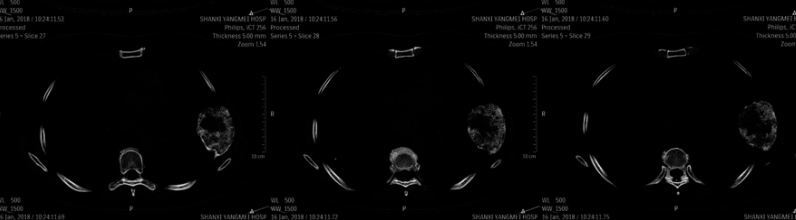

女, 49岁

半年前体检发现左侧肋骨肿块,无疼痛,无外伤,体表未见明显肿块。随后行手术肿块切除。

影像学检查:

(点击查看大图)